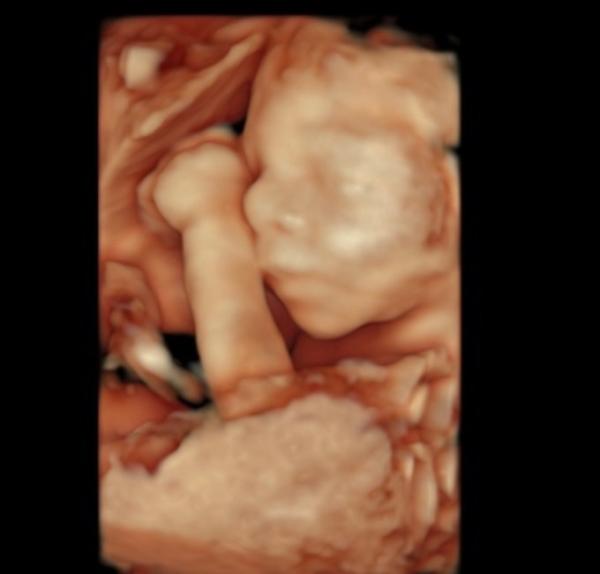

3D Bild hänge ich mal an.